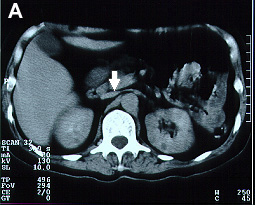

Imagens tomográficas da paciente após a trombose da veia cava inferior. Nota-se a sequência de A para E em que se vê a veia cava normal ao nível das veias renais e abaixo do clipe a veia cava trombosada (aumento do volume com forma circular e halo com captação de contraste)